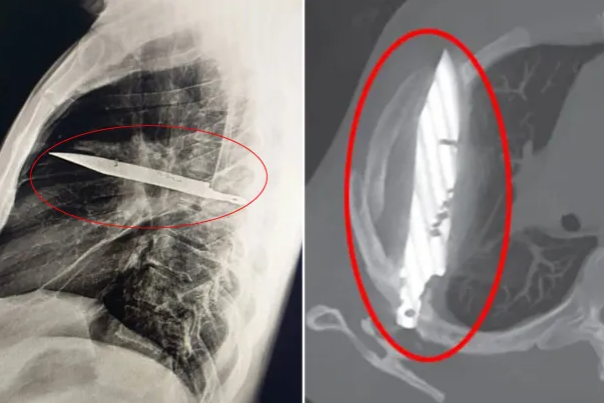

8년 동안 가슴에 거대한 칼이 꽂힌 채로 살아온 한 남성의 사연이 공개됐다.

14일(현지시간) 영국 대중지 더선에 따르면 탄자니아의 한 남성 A씨(44)는 지난 8년간 자신을 괴롭혀온 젖꼭지 부위의 통증 때문에 무힘빌리 국립병원을 찾았다.

병원을 방문한 A씨의 오른쪽 젖꼭지 아래에선 고름 같은 분비물이 흘러나오고 있었다.

가슴 통증의 원인을 진단하기 위해 검사하던 의료진은 흉부 엑스레이 사진을 보고 큰 충격을 받았다. 놀랍게도 A씨의 흉부 중앙에 커다란 칼이 꽂혀 있었기 때문이다.

이름이 밝혀지지 않은 이 남성은 그동안 호흡곤란, 기침이나 열 등이 없었다고 하며 모든 생체 지표도 정상적이었다.

A씨는 어리둥절해 하는 의사들에게 10년 전에 있었던 사건을 들려주었다. 당시 큰 싸움에 휘말렸던 그는 얼굴과 등, 가슴, 배 등에 상처를 입었고 의사의 치료를 받았다고 한다. 그 이후로도 A씨는 가슴 부위의 고름을 알아차리기 전까지는 ‘별 일 없이’ 살아왔다는 것이다.

외사 의사들은 수술을 통해 칼을 조심스럽게 빼냈고, 죽은 조직으로 생긴 고름도 제거했다. 수술 후 10일간 집중 치료를 받은 그는 무사히 퇴원할 수 있었다.

이 놀라운 사례는 최근 외과 사례 보고 저널에 소개됐다.